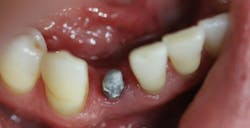

This patient presented with discomfort and mobile teeth Nos. 24 and 25. Extractions were performed, and the area was allowed to heal for six months. Mini-implants were placed in site Nos. 24 and 25 and immediately loaded with temporary crowns. The final splinted restoration was cemented two weeks later.

Figure 7: Following six months of healing

Figure 8: Initial implant placement DIO 3.0 x 16 mm implants